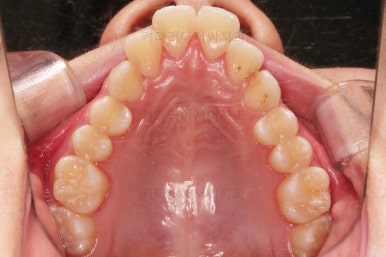

초진 시 입안의 모습입니다.

비밀은 매우 자연스러워 보이지만 아래 앞니 2개가 선천 결손인 상태였습니다.

치아 갯수를 맞추고 튀어나온 앞니를 넣기 위해서 윗니 중간의 작은 어금니를 발치를 했고요.

아래는 통째로 앞으로 끌고 나오기로 했습니다.

윗니는 틈을 점점 줄여가고요.